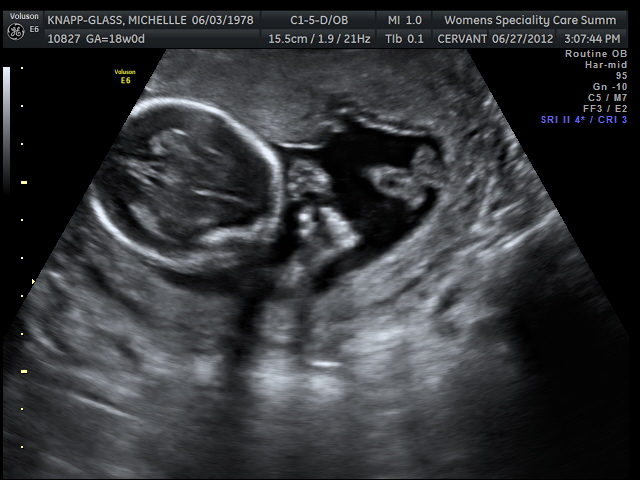

And a pretty nice straight-on face shot where you can clearly make out one of the eyeballs:

Here you can see the top of the baby's head along with his hands and feet. The hand on the bottom is clenched into a fist.